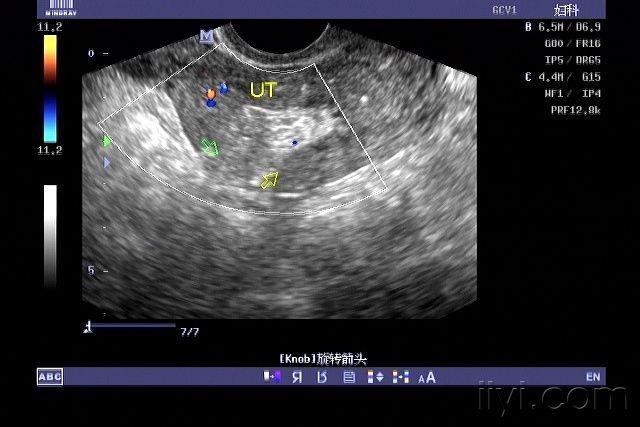

子宫穿孔超声表现图

子宫穿孔超声表现图,子宫穿孔超声图片

危险的人流----子宫损伤,穿孔? - 超声医学讨论版

子宫穿孔? - 超声医学讨论版 - 爱爱医医学论坛 - 医

超声典型病例子宫穿孔

超声诊断子宫穿孔并大网膜嵌顿1例

子宫穿孔超声图片

子宫穿孔彩超下表现

子宫穿孔彩超图